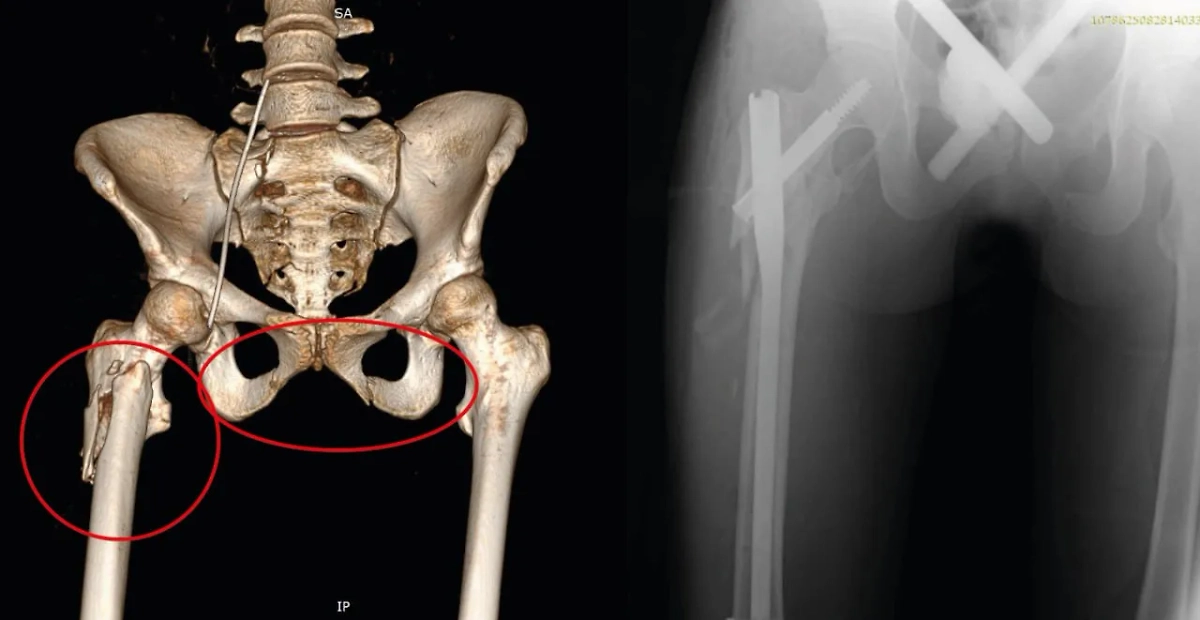

При поступлении девушка находилась в коме с тяжелейшими сочетанными травмами: повреждением головы, грудной клетки и лёгких, переломами таза и бедра, травмой живота. Медики провели экстренные процедуры: обезболивание, массивные переливания крови, дренирование лёгких, а также установили аппараты внешней фиксации на кости таза и бедра.

На пятый день пациентка пришла в сознание, а через неделю её состояние стабилизировалось. Хирурги выполнили остеосинтез — зафиксировали бедренную кость титановым штифтом. Через 20 дней аппарат фиксации с таза сняли, и девушку начали готовить к выписке.